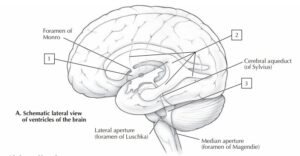

2. Ventrikel lateral berkomunikasi dengan ventrikel ketiga melalui struktur berikut:

3. Apa struktur yang menghubungkan Aquaductus Cerebri (Sylvii)?

7. Pada gambar sistem ventrikel, titik yang berada tepat di belakang pons dan merupakan ventrikel paling caudal adalah… (struktur no.3)CorrectIncorrect -